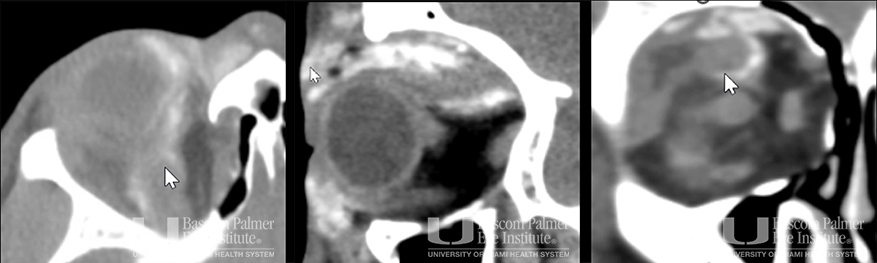

Chronic Orbital Inflammation Secondary to Paint Injury

Chronic orbital inflammation secondary to paint injury.